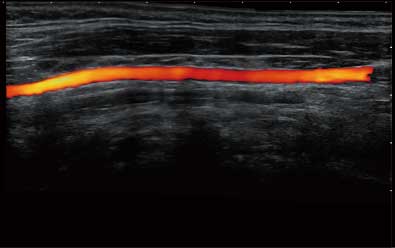

通过对组织运动信息、血流信号及背景噪声进行准确智能的阈值判定,高效提取出微弱血流信号,获得高灵敏度和空间分辨率的血流图像,为临床提供更加真实和丰富的诊断信息。